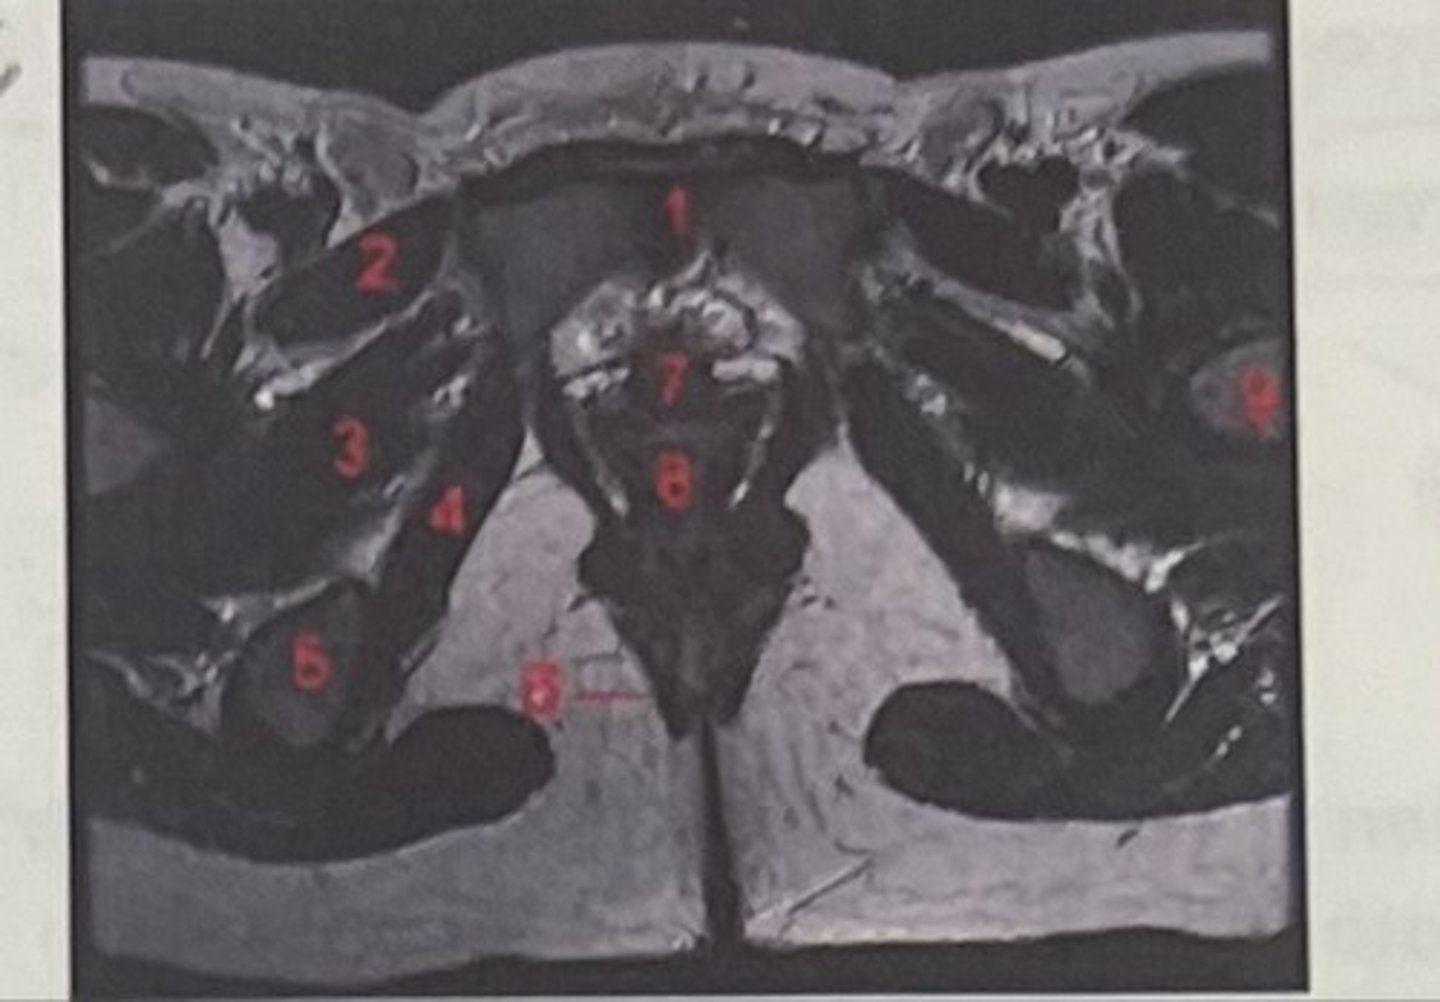

pubic symphysis

What is 1

Pectineus

What is 2

Obturator externus

What is 3

obturator internus

What is 4

ischial tuberosity

What is 5

external spincter

What is 6

Urethra

What is 7

Vagina

What is 8

Femoral nerve

What is 9

Left lung